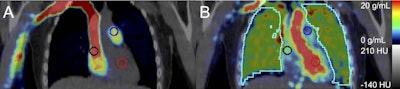

Representative fused coronal PET/CT images after injecting 207 MBq F-18 NOS with 2-cm diameter spherical blood pool search volumes of interest in the right atrium (black), pulmonary artery (blue), and left ventricle (red), with (A) PET-summed uptake 0-15 seconds post injection and (B) PET-summed 37 to 42 seconds post injection with lung volume of interest (cyan). Image and caption courtesy of the Journal of Nuclear Medicine through CC BY 4.0.Participants underwent PET imaging with a radiotracer (F-18 NOS) that binds to a nitric oxide enzyme (iNOS) in pulmonary tissue. iNOS is a PET biomarker associated in prior studies with acute and chronic inflammatory diseases. A blood sample was also obtained to measure cytokine concentrations.

On the PET images, e-cigarette users showed greater binding activity between the tracer and iNOS than cigarette smokers (p = 0.03) and never smoked/vaped controls (p = 0.01), whereas binding in cigarette smokers did not differ from controls (p > 0.1), according to the results.

Moreover, F-18 iNOS binding in the lung imaging correlated significantly with blood concentrations of tumor necrosis factor alpha (TNF-a) (Spearman's rank correlation = 0.87, p = 0.05) in e-cigarette users. TNF-a is a potent inflammatory cytokine that responds to injured lung tissue.

"We find evidence that [e-cigarette] use causes a unique inflammatory response in the lungs, reflected by PET measures of iNOS expression and correlations with inflammatory biomarker concentrations," the authors wrote.